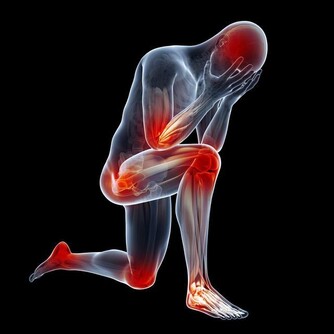

一、血管發生堵塞,腳會出現3個異常,若佔一個,提醒你要注意了

*****1、異常一:腳麻*****

血管堵塞,血液不流通,會導致腳經常發麻。

*****2、異常二:腳走路會不穩*****

血管堵塞,會發生走路不穩易摔倒的現象。

*****3、異常三:腳腫*****

血管堵塞,血液的流通受阻,進而就會造成腳經常水腫。